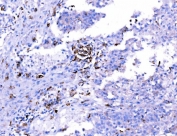

IHC staining of FFPE human Hashimoto's thyroiditis tissue with Endophilin A1 antibody. HIER: boil tissue sections in pH8 EDTA for 20 min and allow to cool before testing.